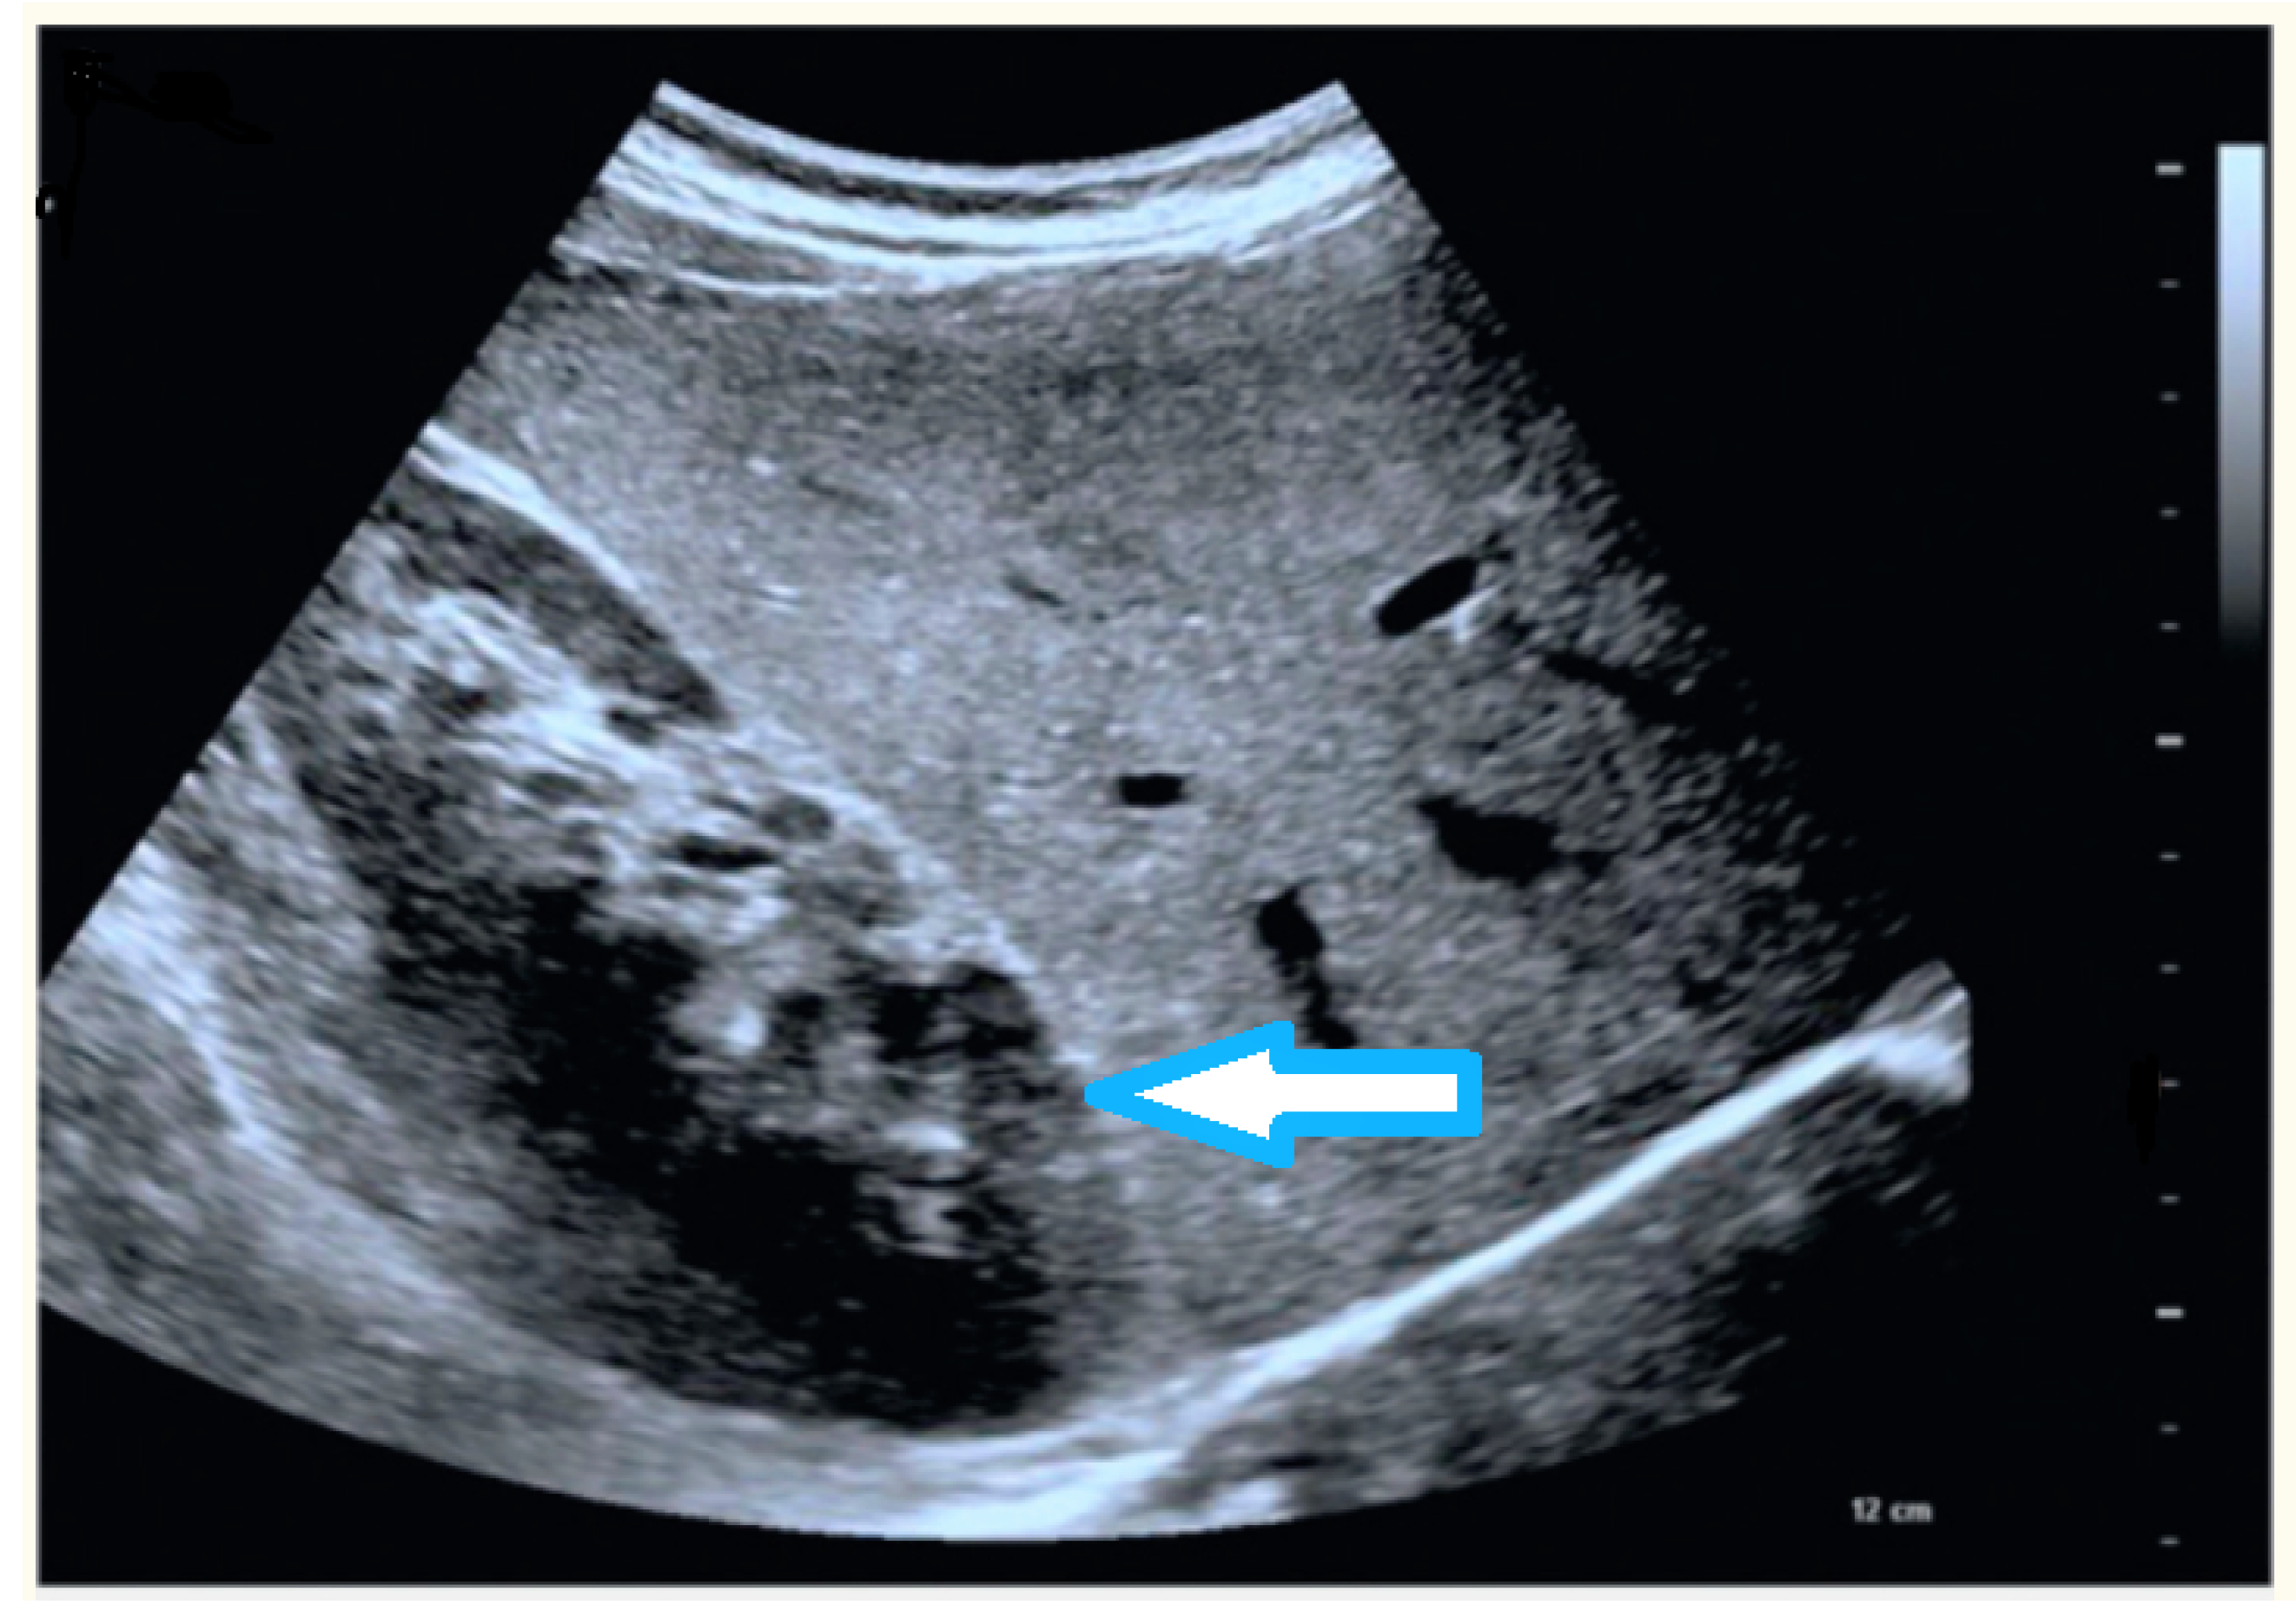

4.4. Liver

- focal liver lesions, solid formations that can be benign or malignant,

- liver fibrosis, excessive accumulation of extracellular matrix proteins, such as collagen,

- fatty liver or liver steatosis, conditions based on the accumulation of excess fat in the liver,

- liver tumors.